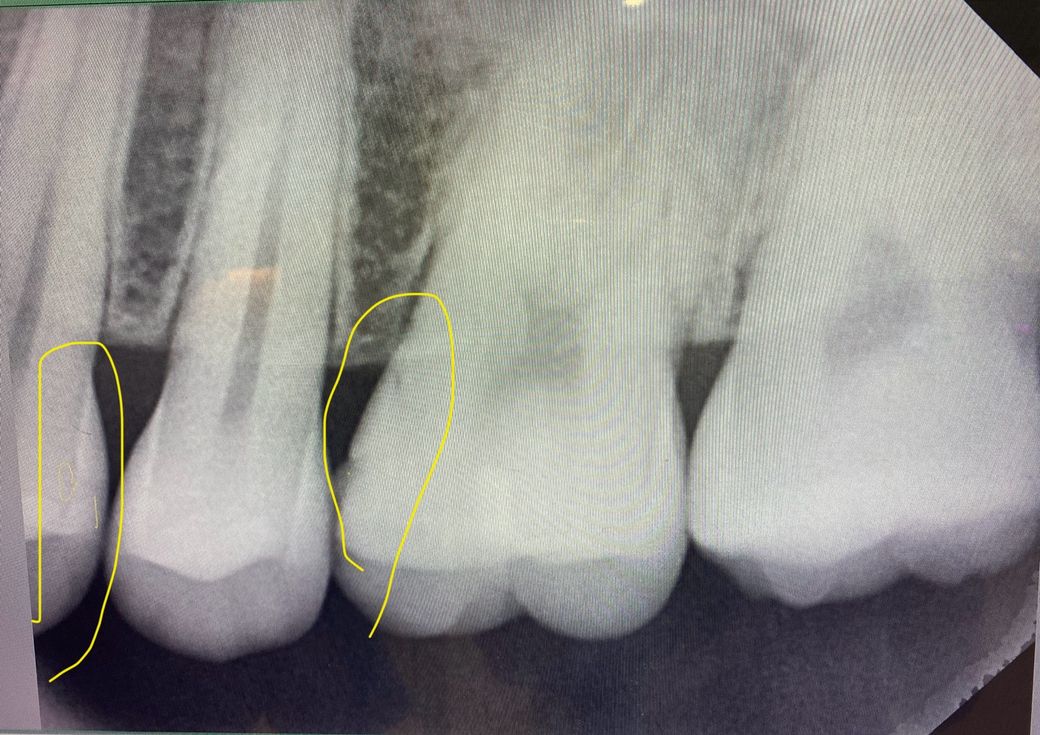

치과 진료 3:1로 치료하지 말자고 하셨는데 지켜봐도 될까요?

치과 한곳에서 육안으로 인접면 충치와 어금니 2차충치

확인하고 인레이 70만 또는 레진 30만

진단 받았어요

3곳을 더 돌았는데

3곳 모두 인접면 충치가 보이긴 하지만 증상도 없고

엑스레이, 치근단 사진을 봐도 너무 작아서

6개월 마다 경과를 지켜보자

그리고 2차충치는 안보이고 많이 닳긴했지만 이상 없다

마지막 치과는 교수 겸임하고 논문도 쓰시는 원장님이셨는데 이러면 지켜봐도 될까요?